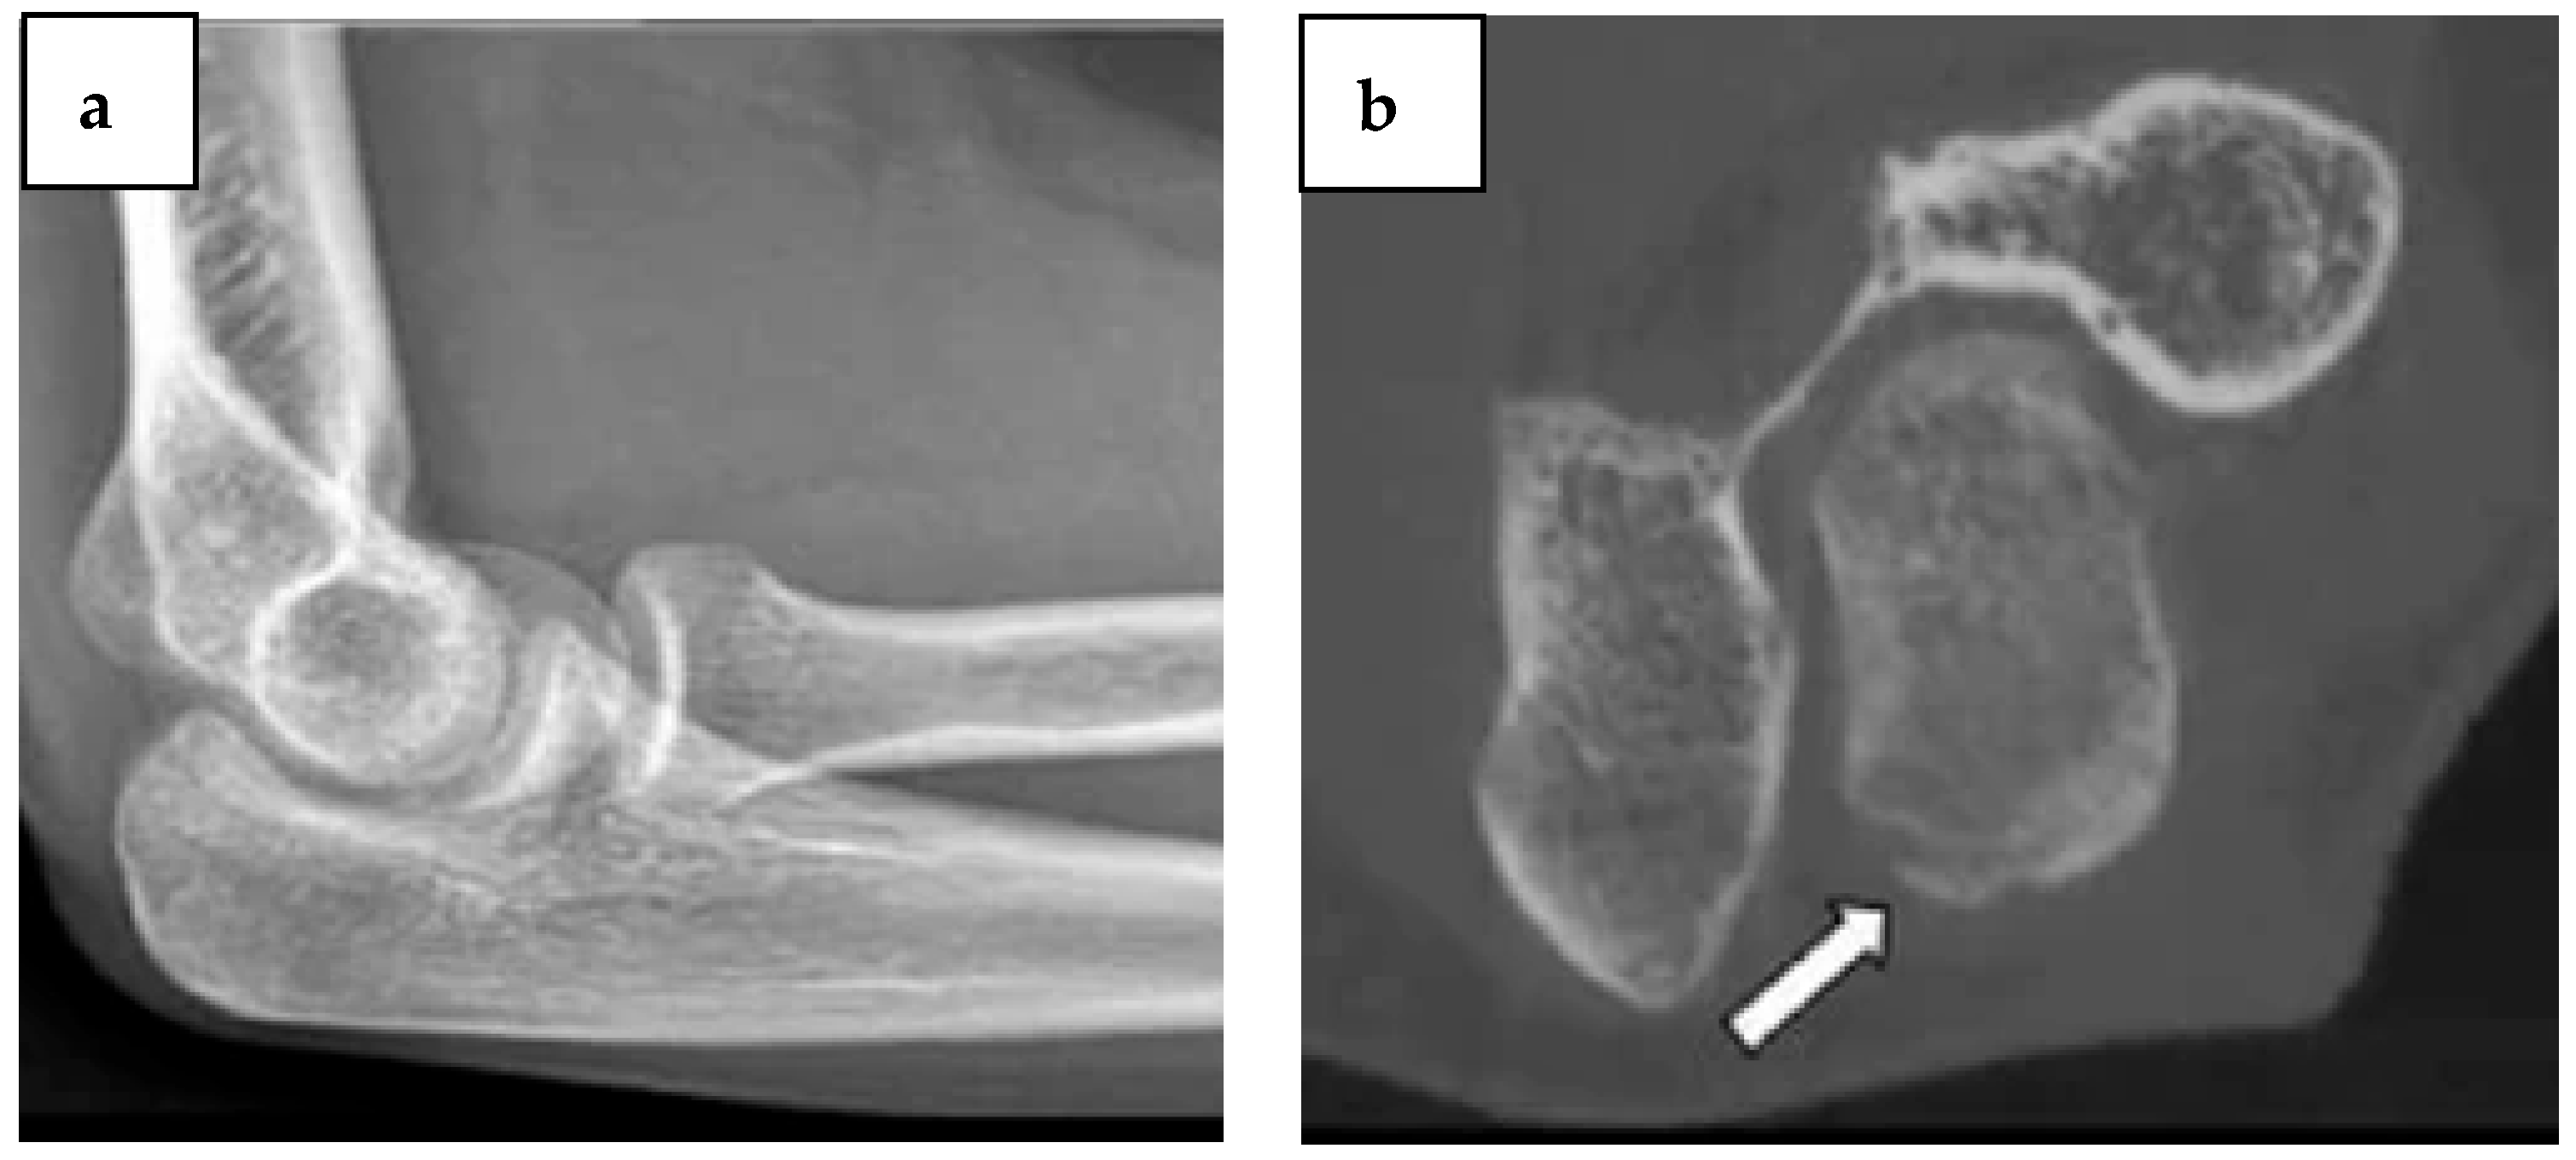

- Vanhoenacker, F.M.; Desimpel, J. Cone Beam CT of Trauma of Small Bones and Joints. Semin Musculoskelet Radiol 2017, 21, 290–302. [Google Scholar] [CrossRef] [PubMed]

- De Smet, E.; De Praeter, G.; Verstraete, K.L.A.; Wouters, K.; De Beuckeleer, L.; Vanhoenacker, F.M.H.M. Direct comparison of conventional radiography and cone-beam CT in small bone and joint trauma. Skelet. Radiol. 2015, 44, 1111–1117. [Google Scholar] [CrossRef] [PubMed]

- Posadzy, M.; Desimpel, J.; Vanhoenacker, F. Cone beam CT of the musculoskeletal system: Clinical applications. Insights Into Imaging 2018, 9, 35–45. [Google Scholar] [CrossRef] [PubMed]